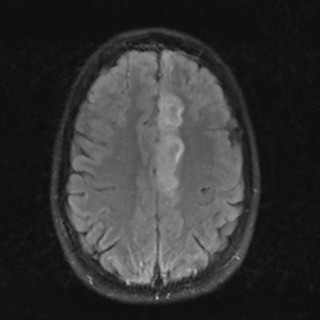

En mann i 70-årene ble henvist hematologisk poliklinikk grunnet redusert allmenntilstand og anemi. Blodprøver viste hemoglobin 9,7 g/dl (13,4–17,0), gjennomsnittlig cellevolum i de røde blodcellene (MCV) 115 fl (82–98), leukocytter 3,0 · 10 9/l (3,5–11,0), trombocytter 187 · 10 9/l (145–348), folat 7,2 nmol/l (> 8,0), kobalamin 693 pmol/l (175–700) og ferritin 831 µg/l (34–300). Tilstanden ble oppfattet som megaloblastisk anemi på grunn av folatmangel, og man startet med folatbehandling. Kontroll etter to måneder viste vedvarende anemi med hemoglobin 9,4 g/dl. Benmargsutstryk med May-Grünwald...